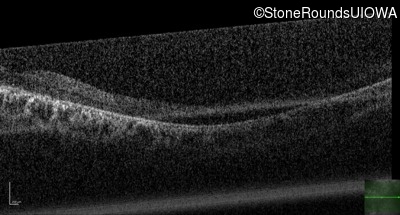

Optical Coherence Tomography - Right - 10/160

Exemplar / OCT Stack